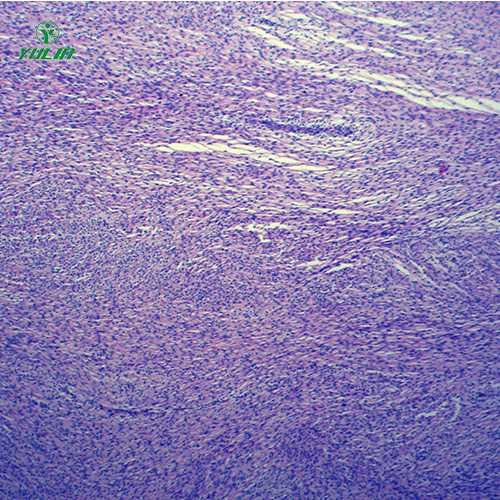

湖南炎症病理玻片

产品内容说明 /Product description

人体病理切片,炎症病理玻片,炎症病理玻片价格